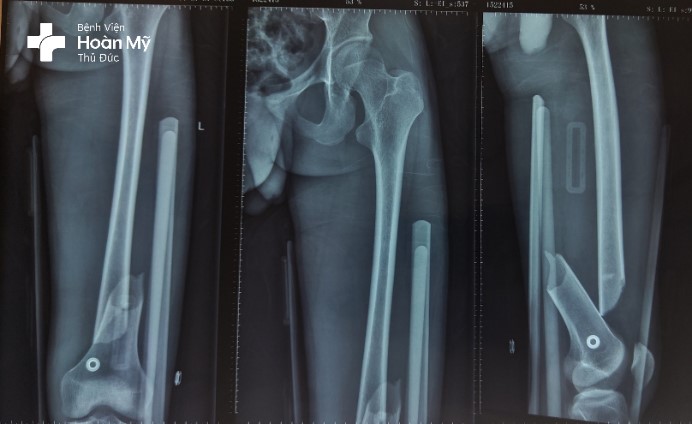

X-quang đùi trái trước mổ gãy 1/3 dưới thân xương đùi trái di lệch nhiều

Hình chụp X-quang sau mổ: kết hợp xương nẹp vít